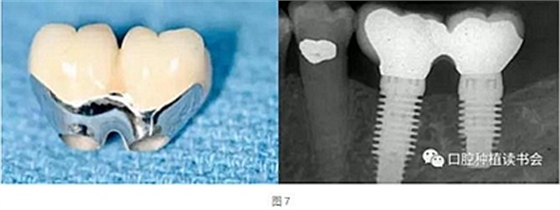

天然牙的預(yù)備通常限制刃狀邊緣的使用以避免最終修復(fù)體外形過凸。沒有具體的研究表明凹形邊緣完成線比其他的完成線形態(tài)更優(yōu)越,但易于預(yù)備的特點是選擇它們的理由,而且避免了修復(fù)體過大。修復(fù)學(xué)中存在幾種常見的刃狀邊緣預(yù)備的適應(yīng)證,因為它們只需要極小的切削量。適應(yīng)證包括:①種植體基臺(圖7);②磨牙和前磨牙的根分叉區(qū)域;③下頜切牙的鄰間隙區(qū)域;④下頜后牙的舌側(cè)面;⑤軸面特別凹(非常凸的軸向表面);⑥傾斜超過15°的基牙軸面。